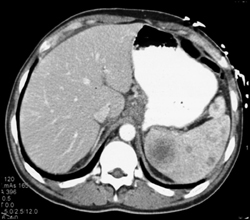

Ampullary Cancer - Look Inside Common Bile Duct